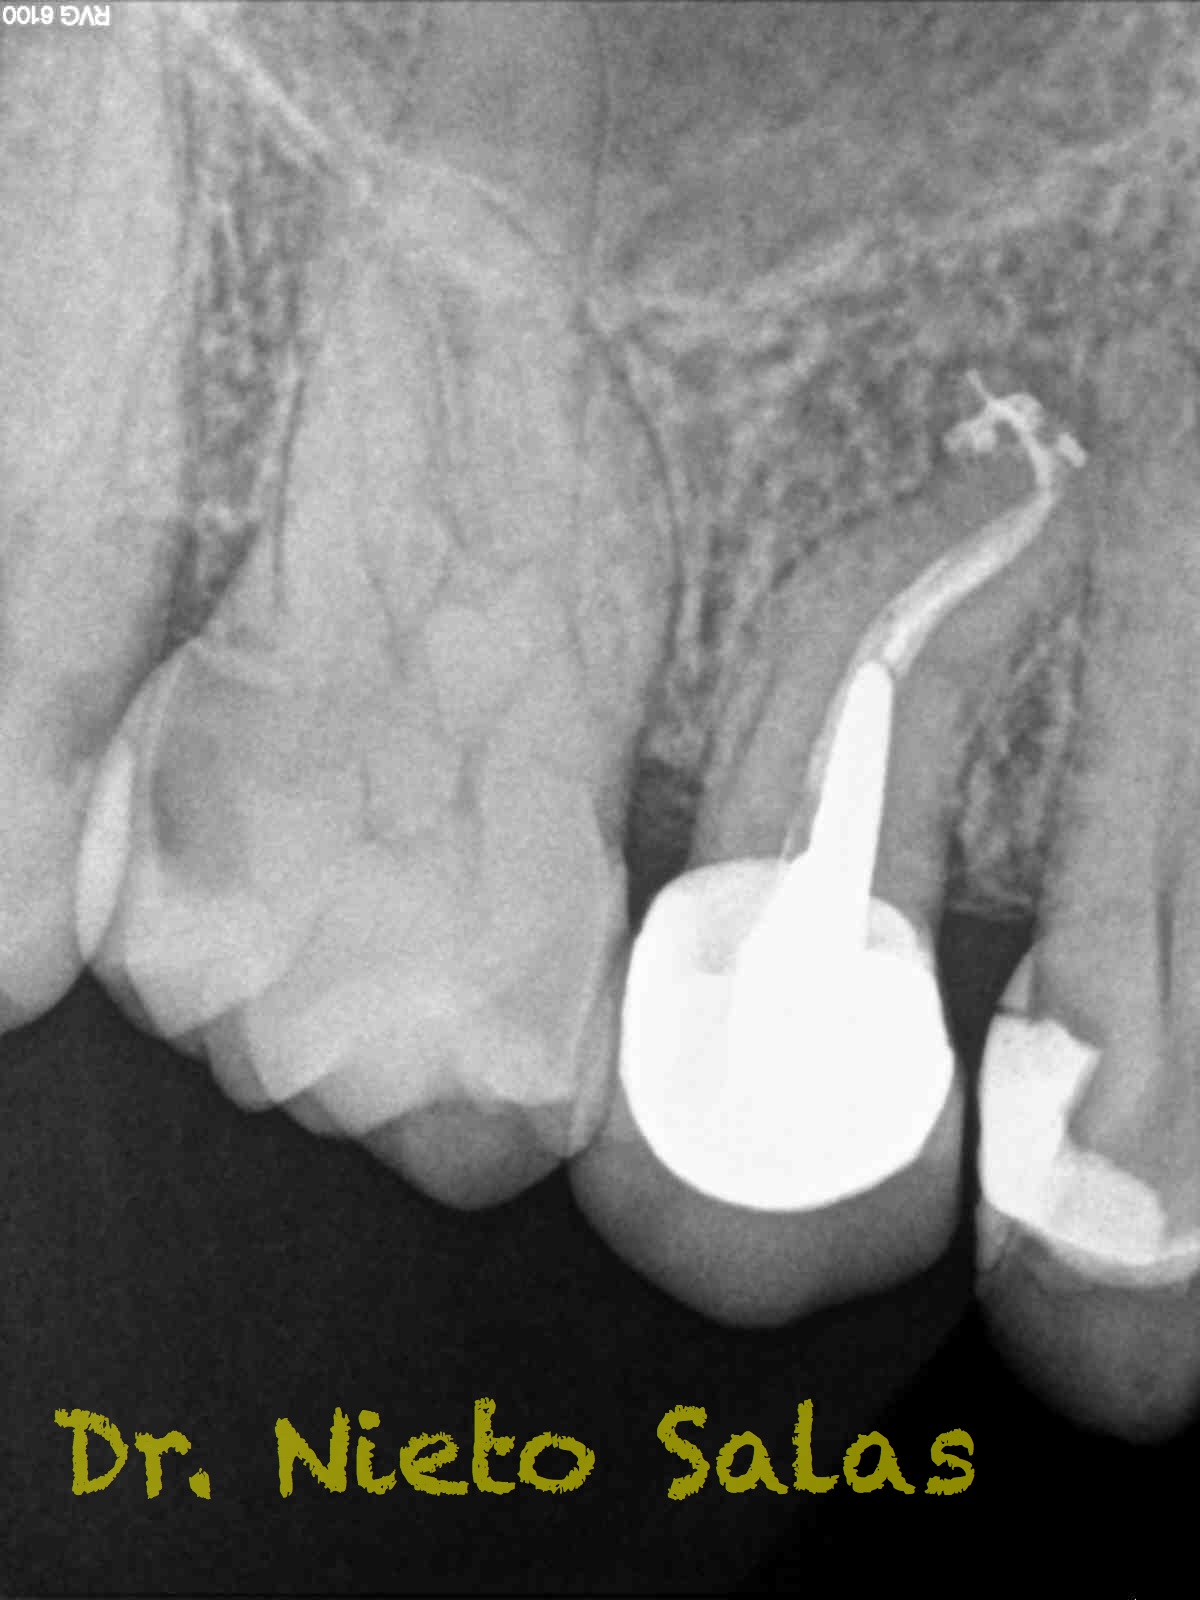

Y  de forma muy similar en el caso B; en este caso el paciente vino a la revisión a los 9 meses evidenciado el éxito en el tratamiento:

Con respecto a lo puramente endodóntico, la verdad que fueron unos casos de verdadero estrés para no perder la permeabilidad ni la long de trabajo, con técnica corona-apice y con un diametro apical de 20, instrumentado solo la parte apical con limas de Mtwo , la parte coronal me ayudé de ultrasonidos. No sé, que más contarte con respecto a la conformación de los conductos.

La verdad, no me planteé la posibilidad de la obturación con Thermafil, se trataba de un caso con un sistema de conductos con un itsmo coronal, y pienso que la obturación con sistema de ola continua me garantizaba un mejor sellado.